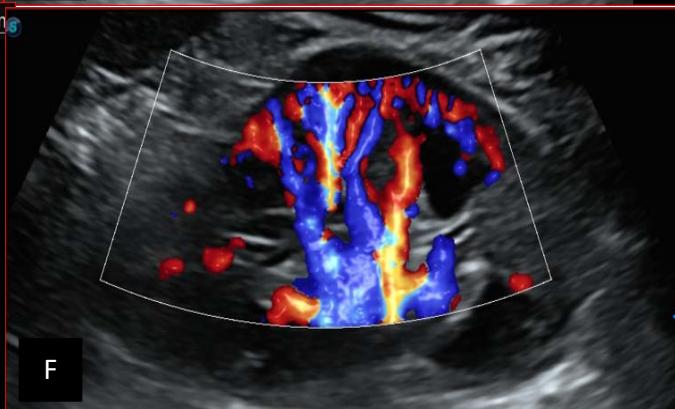

Figure 6: 9-year-old sickle cell patient, referred for abdominal bloating with significant collateral venous circulation, in whom we noted: Image A: mass, Image B: healthy renal stump, inferior polar; Image C: left transmedian extension, Image D: thrombosis of the vena cava segments: supra, retro and sub hepatic, sparing a part of the supra hepatic vena cava segment over $30~\mathrm{mm}$. Image: Ascites of great abundance, Image F: normal left kidney, Image G: splenic microcalcifications, Image H: celiac adenopathy, Image I: sub pleural pulmonary nodules with the biggest measuring $3.88 \times 3.81 \mathrm{~mm}$, Image j: left pleurisy of great abundance. Source: Dr. Frederick Tshibasu Tshienda database.